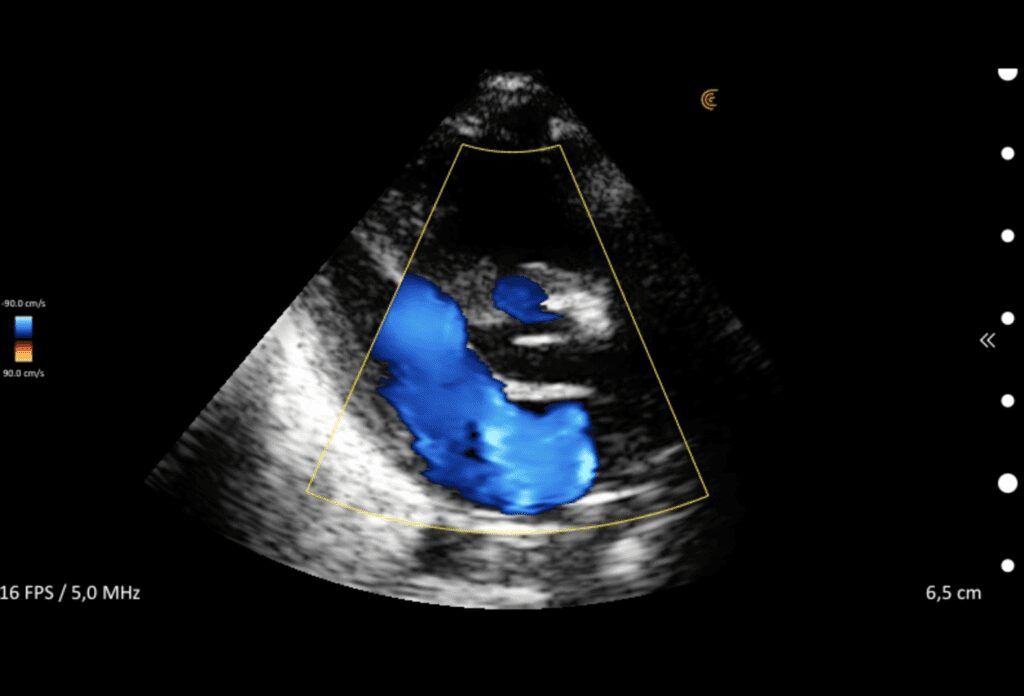

Color/Power Doppler Farb-/Powerdoppler Doppler couleur/puissant Doppler de color/potencia | |

Vascular